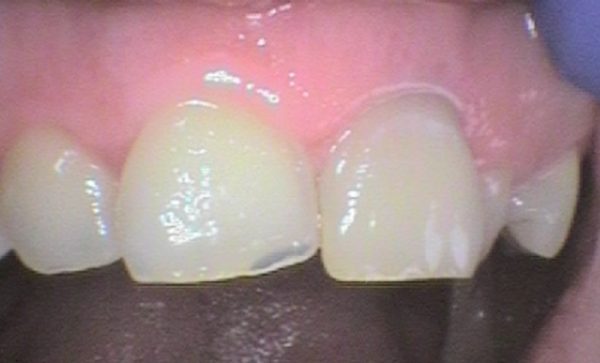

Case 17